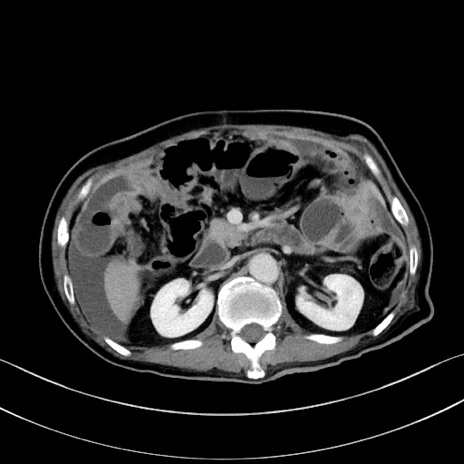

症例28(横断像)

【症例】60歳代男性

【主訴】嘔吐

【現病歴】胃癌にて胃全摘後。食思不振が悪化し、夜中に嘔吐することがある。

【既往歴】胃癌、胃全摘、脾摘、胆摘後

【データ】WBC 5900、CRP 10.56